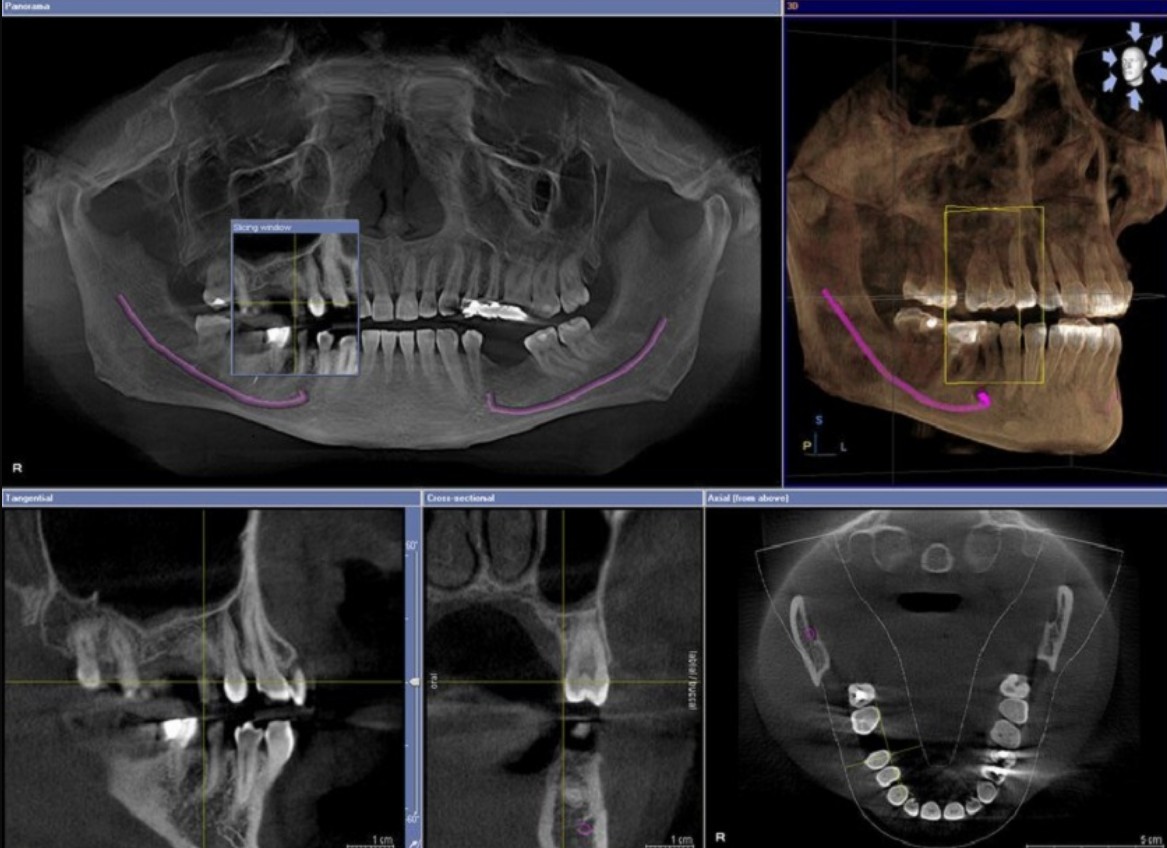

Vì vậy, khi phát hiện răng khôn mọc lệch hoặc đau kéo dài, người bệnh nên đến nha khoa để chụp CT Cone Beam 3D, giúp xác định chính xác vị trí và mối liên hệ thần kinh trước khi quyết định nhổ.

• Công nghệ hỗ trợ:

• Máy Piezotome (siêu âm) giúp cắt xương chính xác, giảm đau và sưng nề.

• Chụp CT Cone Beam 3D giúp quan sát rõ mối quan hệ giữa răng và dây thần kinh, giảm rủi ro tổn thương.